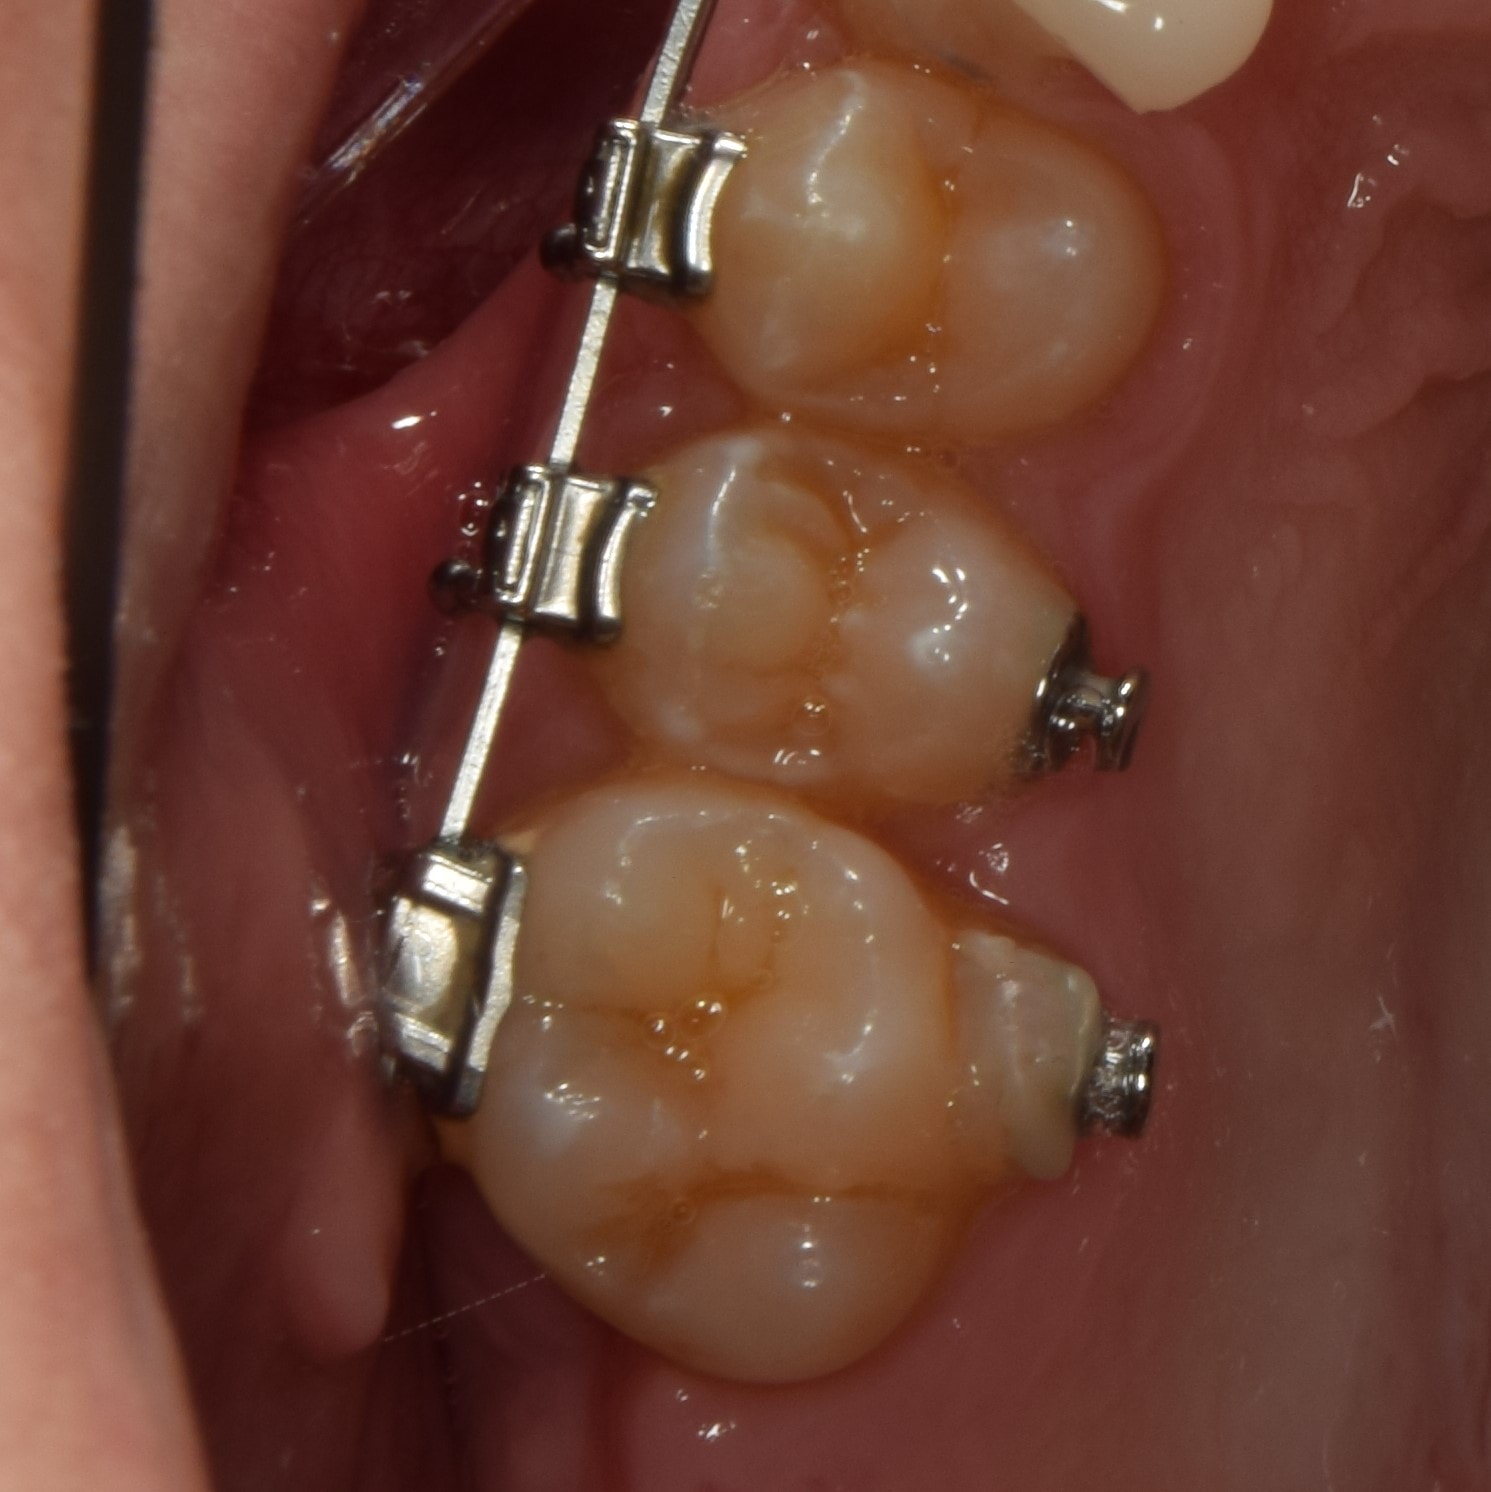

Inlay, onlay, overlay

Sérült, destruált fogak ellátására alkalmazott, az őrlő, kisőrlő fogakra ragasztott, fogtechnikus által készített, fogpótlásnak nem minősülő fogtömés, ismertebb nevén betét. Ha a fog kifúrása után a megmaradt egészséges foganyag már túl kevés ahhoz, hogy egyszerű tömést készítsünk, de még túl sok, hogy a fogat egy koronához teljesen lecsiszoljuk, úgy a betét az ideális választás. Kiterjedése szerinte inlayàonlayàoverlayről (növekvő sorrend) beszélhetünk. Nagyon sokszor használjuk gyökérkezelt és/vagy letört fogak ellátására. A megfelelő biomechanikai irányelvek alapján elkészített betétek hosszútávon sikeresebbek, mint az egyszerű fogtömések. A betétek elkészítése a töméseknél bonyolultabb, legtöbbször két időpontot vesz igénybe. Az első alkalommal történek a fog csiszolása, majd lenyomatvétel és ideiglenes fogpótlás készítése, majd a második alkalommal ragasztjuk be a kész betétet. Anyagukat tekintve klasszikus tömőanyagból, kerámiából vagy aranyból készülhetnek. Mai napig az arany az egyik legjobb anyag ilyen célra! A betét tehát egy jó választás a lehető legtöbb egészséges foganyag megőrzésére, viszont a kezelőorvos egyéni megítélésére kell hagyatkoznunk.